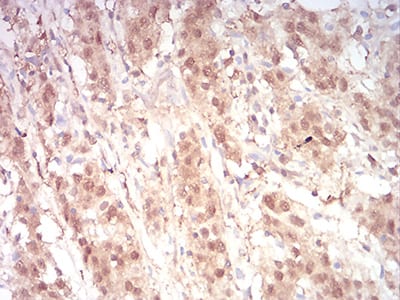

Immunohistochemical analysis of paraffin-embedded human stomach cancer tissues using CTLA4 mouse mAb with DAB staining

Immunohistochemical analysis of paraffin-embedded human cervical cancer tissues using CTLA4 mouse mAb with DAB staining